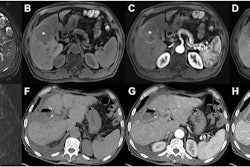

Imaging findings on MRI can help clinicians understand a tumor's "biological behavior" and thus improve their ability to make an accurate prognosis regarding disease recurrence, the group explained: Features such as ill-defined tumor margins, an absence of a tumor capsule, and enhancement of the area around the tumor the arterial phase may indicate that the cancer is aggressive.

These factors were used to calculate patients' risk of recurrence (a recurrence score was determined using MRI imaging data; a high risk score was equal to or higher than 110).

It's not surprising that the investigators found that higher risk scores were predictive of liver cancer recurrence after ablation (recurrence scoring had a sensitivity of 89% and specificity of 95%); they found that the factors included in the development of the algorithm were predictive of recurrence as well.